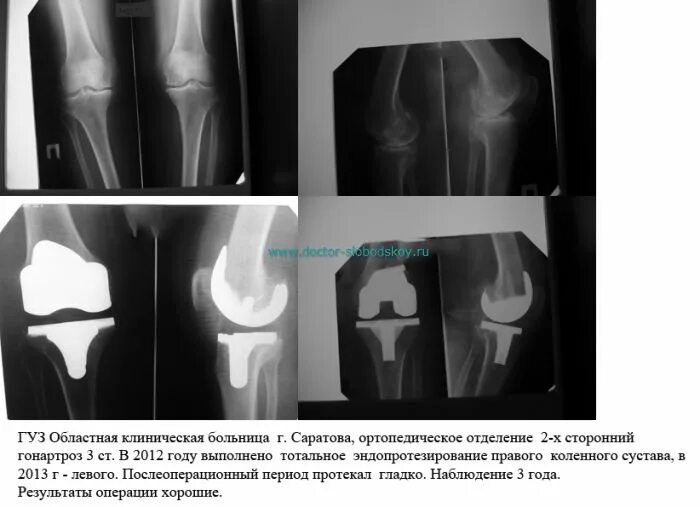

Можно ли эндопротезом делать мрт